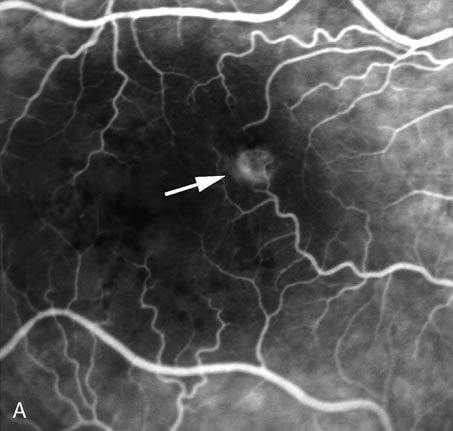

Fig. 16. Subfoveal, juxtafoveal, and extrafoveal choroidal neovascular membranes. A and B. Large subfoveal choroidal neovascularization (CNV) in a 69-year-old man with blood and pigment blocking central fluorescence on both the early-phase (A) and late-phase (B) photographs. The hypofluorescence surrounding the membrane is commonly seen in CNV and may be due to lipofuscin. C. Juxtafoveal CNV in a 37-year-old man with idiopathic CNVM. D. Cuticular drusen in same patient as in C were asymptomatic. E. Years later, this same patient developed a large extrafoveal CNV with central macular pigment abnormalities. A large neurosensory detachment was responsible for the disappearance of the drusen. (Courtesy of Dr. Kenneth G. Noble.)

Conventional laser thermophotocoagulation is the treatment of choice for extrafoveal, well-defined, classic CNV. Photodynamic treatment (PDT) is the treatment of choice for subfoveal, predominantly classic CNV. FA is used to localize the lesion in relation to the fovea, classify the subtype, choose the type of procedure, and guide the treatment (Figs. 18, 19, and 20).56–73